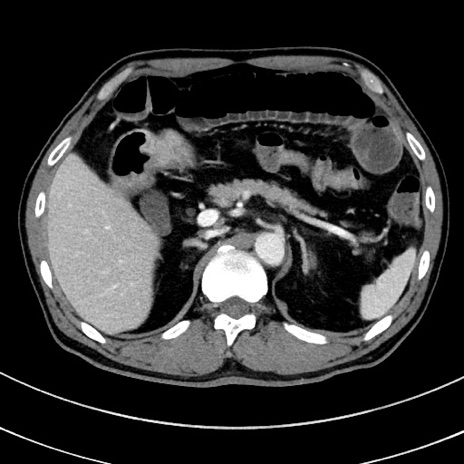

冠状断像

【症例】 60歳代男性

【主訴】 黒色吐物

【現病歴】 4日前から嘔気自覚、2日前の朝食後にも嘔気あり、自分で手で嘔吐反射起こし嘔吐したところ血が混ざっていたため受診。

【既往歴】 5年前汎発性腹膜炎を伴う急性虫垂炎で手術、高血圧、前立腺肥大症、高脂血症

【身体所見】 腹部正中に手術癩痕あり 腹部平坦・軟圧痛なし膨満感あり

【データ】WBC 8400、CRP 4.54